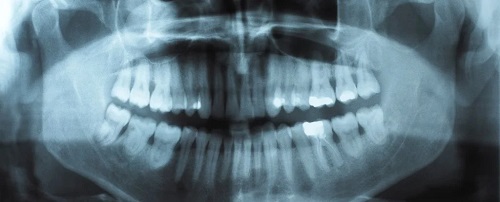

Стоматологический осмотр поможет выявить признаки скрежета зубов и стискивания челюстей, которые могут включать трещины в зубах и пломбах, изношенные коронки или клыки (так называется приподнятый край зуба), а также нежные челюстные мышцы. Также часто отмечается напряжение мышц по бокам головы и шеи.